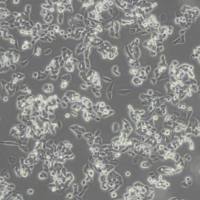

细胞中文名称:KMH2人甲状腺癌细胞(未分化)(带STR鉴定)

| 名称 | KMH-2 (人甲状腺癌细胞(未分化)) (STR鉴定正确) |

| 种属 | 人类 |

| 年龄(性别) | 男性,71岁 |

| 组织来源 | 甲状腺未分化(间变性)癌 |

| 生长特性 | 贴壁细胞 |

| 细胞形态 | 纺锤状细胞、伴有巨细胞 |

| 生长培养基 | 45% DMEM+45% RPMI-1640+10% FBS+1%P/S |

| 推荐传代比例 | 1:2-1:4 |

| 推荐换液频率 | 2~3次/周 |

| 倍增时间 | ~58小时 (PubMed=11686581) |

| 冻存条件 | 冻存液:55% 基础培养基+40%FBS+5%DMSO温度:液氮 |

| 培养条件 | 气相:空气,95%;CO2,5%温度:37℃ |

| 保藏机构 | JCRB; JCRB1066 |